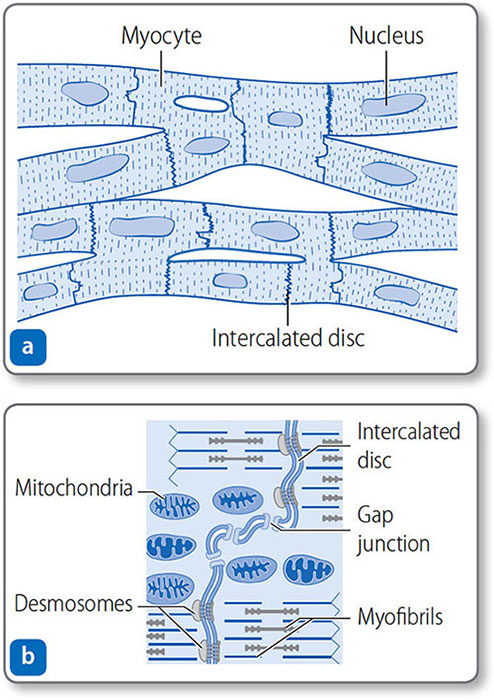

Cardiomyocytes

Cardiomyocytes are branched, tubular cells with a central nucleus (Figure 1.20). They connect end to end at intercalated discs. The discs contain desmosomes that anchor cells together, and gap junctions, which allow action potentials to conduct freely between cells.

Figure 1.20: Cardiac muscle. (a) Cardiomyocytes are branched, nucleated, elongated, tubular cells joined at intercalated discs. (b) Close up of an intercalated disc. Desmosomes anchor cells, and gap junctions allow ions to pass freely between cells.